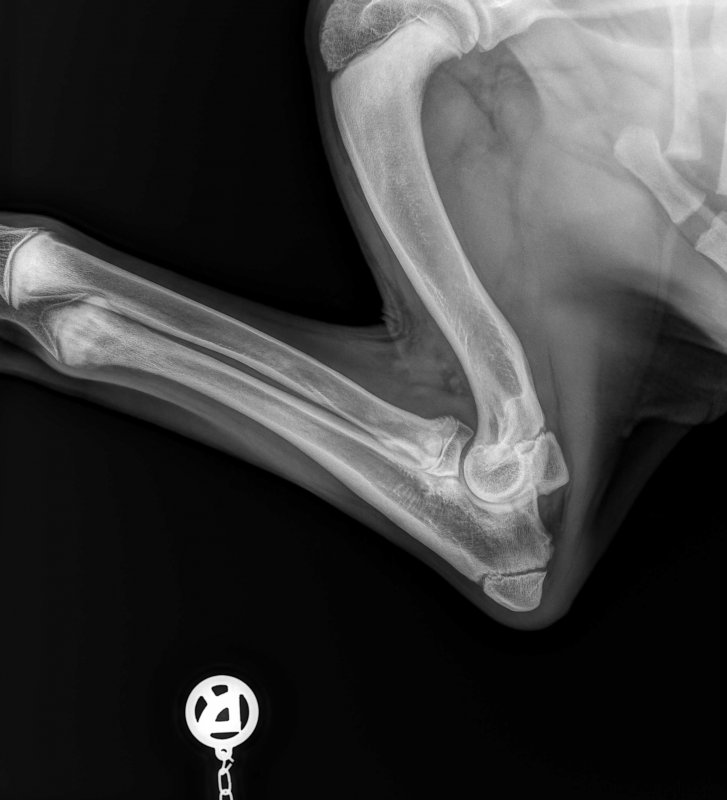

Sooo habe nun auch die Nachher Bilder ich stelle nochmal beide rein also vorher und nachher.

Da sieht man schön den Knochenbruch der Ulnaresektionsosteotomie. Sind aber wohl unterschiedliche Postionen vor und nach der OP der Aufnahmen

Auf dem oberen Bild sieht man deutlich das Fragment auf der rechten Seite das entfernt wurde. Selber am Gelenk hab ich es auch nur mit der Unterstützung vom Arzt gesehen. Also bei den seitlichen Aufnahmen da erkenne ich ohne Anleitung auch nichts. Die ct Aufnahmen checkt man auch nur mit Arzt Erklärung